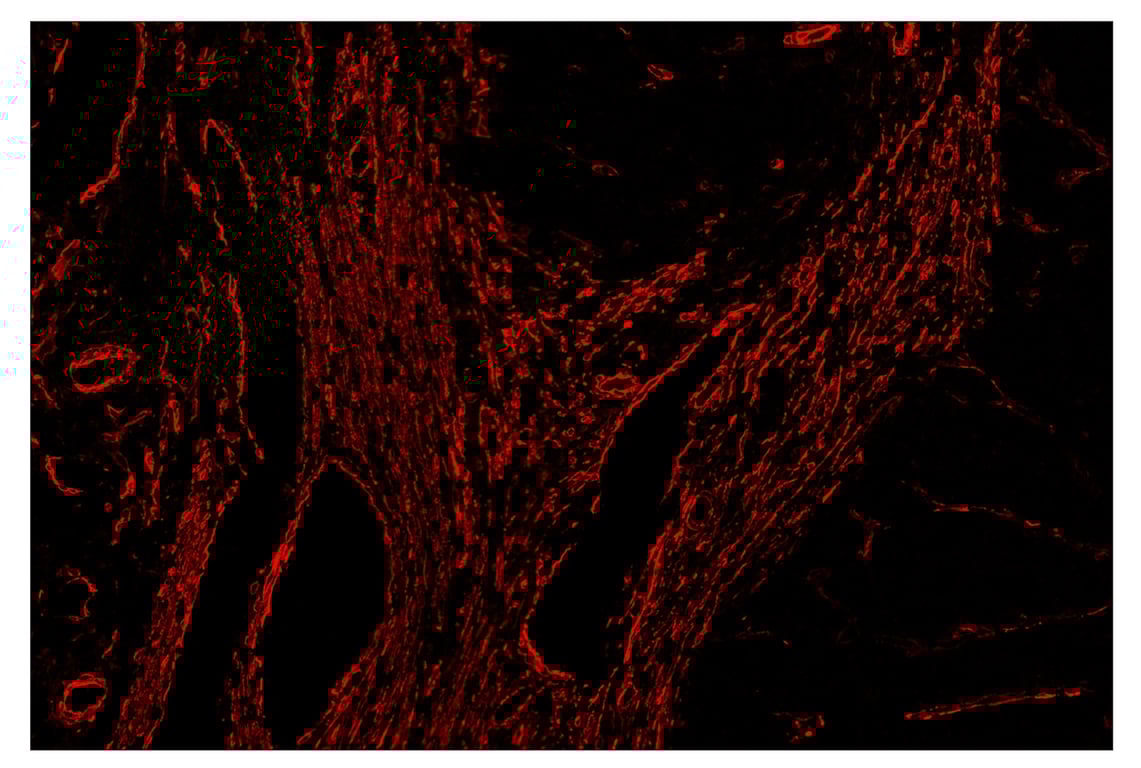

SignalStar™ immunohistochemical analysis of paraffin-embedded human gastric adenocarcinoma using α-Smooth Muscle Actin (D4K9N) & CO-0024-647 SignalStar™ Oligo-Antibody Pair #63902 (red). All fluorophores have been assigned a pseudocolor, as indicated. Staining was performed on the BOND RX by Leica Biosystems.

Immunohistochemistry Image 5: alpha-Smooth Muscle Actin (D4K9N) & CO-0024-488 SignalStar<sup>™</sup> Oligo-Antibody Pair